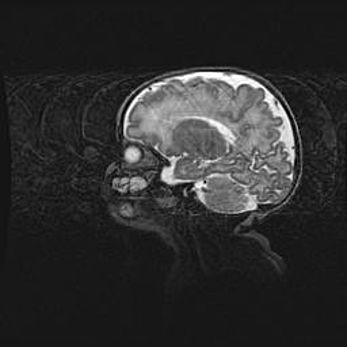

Аномалия Денди-Уокера. Признаки гипоплазии мозолистого тела.

Возраст: 5 месяцев 3 дня

Вес: 5550 г

Пол: мужской

Окружность головы: 39 см

Срок гестации: 40 недель

Аномалия Денди-Уокера – это порок развития головного мозга, для которого характерна триада симптомов: гипотрофия или аплазия червя мозжечка и/или полушарий мозжечка, расширение четвёртого желудочка с формированием ликворной кисты задней черепной ямки, гипертензионная гидроцефалия различной степени.

Гипоплазия мозолистого тела относится к дефектам внутриутробного этапа развития мозговой ткани, возникающим в процессе закладки структур головного мозга, что происходит на начальных этапах развития эмбриона.